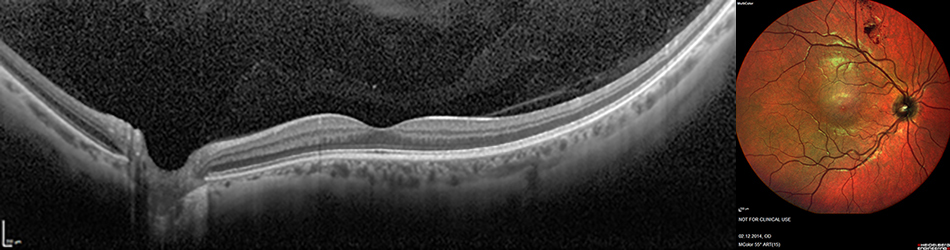

Rechts: MultiColor Fundusbild aufgenommen mit dem SPECTRALIS Weitwinkel Bildgebungsmodul von Heidelberg Engineering

Das Weitwinkel Bildgebungsmodul ermöglicht eine Bildgröße von 55° für alle SPECTRALIS Fundusbildgebungs-Modalitäten wie MultiColor, BluePeak, Infrarot Reflexion, Angiografie sowie für die OCT-Bildgebung. Dabei erleichtert die Darstellung der Makula, des Sehnervenkopfes und der Gefäßbögen in einer Aufnahme eine umfassende Diagnostik. Die hochaufgelösten, kontrastreichen Scanning Laser Aufnahmen mit dem Weitwinkel Bildgebungsmodul bieten diagnostische Möglichkeiten, welche über die konventionelle Fundusfotografie hinausgehen.

Scanning Laser Fundusbildgebung in Kombination mit OCT hat sich zu einer unverzichtbaren Technologie in der Augenheilkunde entwickelt und wird schon heute in vielen Praxen erfolgreich als wichtiges Hilfsmittel zur Diagnose und Verlaufskontrolle von Erkrankungen wie zum Beispiel Glaukom, Altersbedingte Makuladegeneration (AMD) und Diabetische Retinopathie eingesetzt.